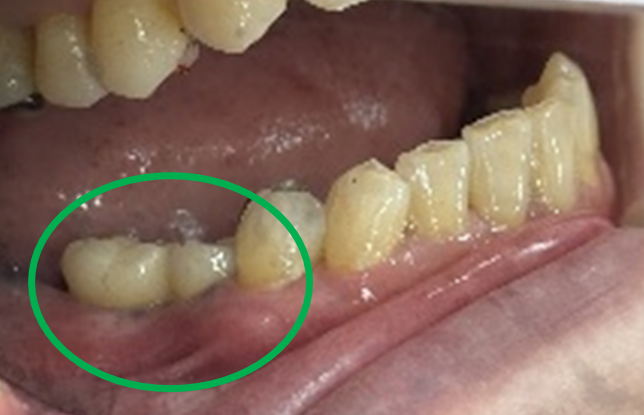

Before

※赤丸は、歯根が破折していたため抜歯しました

※黄色丸は、2006年10月に埋入したインプラント

After

※緑丸は、今回埋入したインプラント

左上第二小臼歯と第一大臼歯の歯根が破折していたため、保存することができず抜歯しました。第一小臼歯は、すでにありませんでしたので、2本抜歯後3本欠損のところにインプラントを2本埋入しました。

所感

2006年10月に右下と左下の欠損部分にインプラント治療をしました。今回も左上の歯を失ったところは、インプラント治療を希望されました。